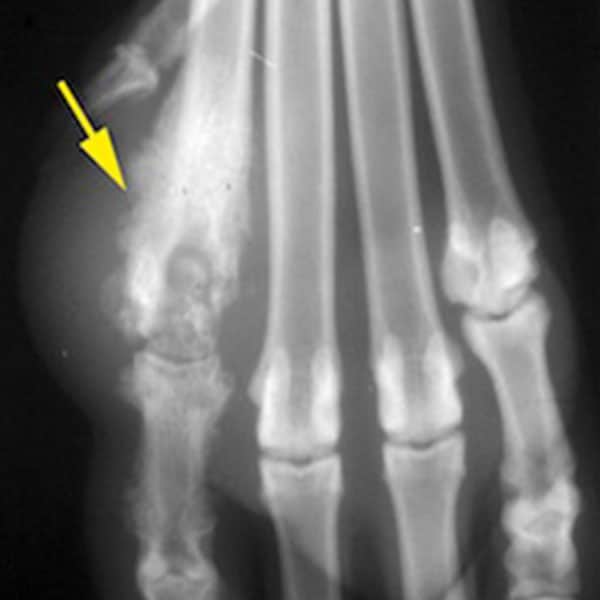

Les radiographies des membres peuvent montrer des déformations des os et parfois des fractures, souvent passées inaperçues.